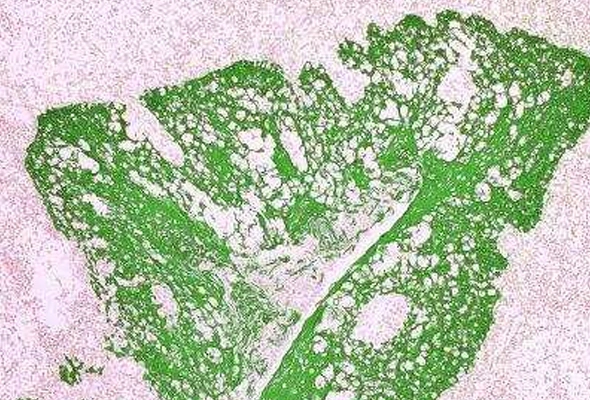

Immunohistochemistry (IHC/ICC) 면역조직염색, 면역세포염색에 이용되는 염색 kit, 조직슬라이드 등을 제공합니다. [Novus] IHC Tissue Slides [Novus] MolBoolean Mouse/Rabbit Assay Kit [Novus] Tissue Glue Kit [Novus] Tissue Microarrays (TMA) [Novus] VECTASTAIN ABC Detection Kit [Novus] Vector TrueVIEW Autofluorescence Quenching Kit